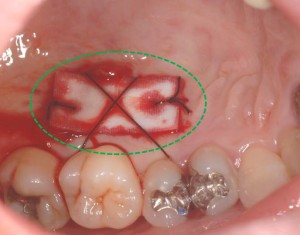

上顎裏側の緑○部分より移植し、創傷治癒材でカバーしています。

動かない歯茎(歯肉)が形成され、ブラッシングが行いやすくなっただけではなく、歯と付着することで歯周組織の健康も維持されやすくなりました。